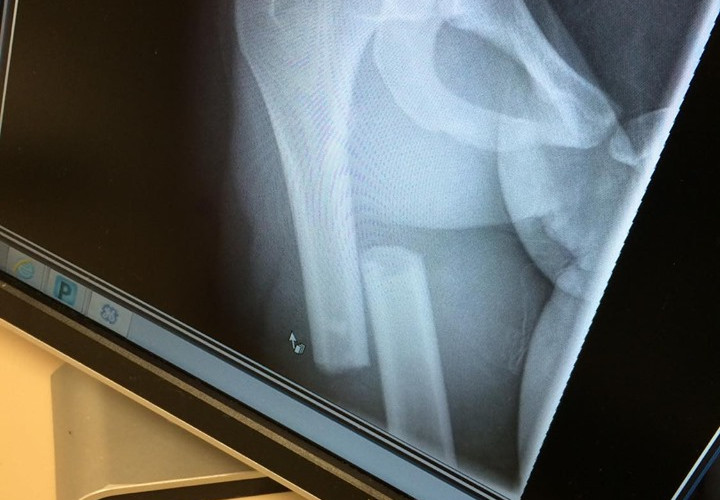

After getting to Wellington Regional Hospital and LOTS of morphine later, I was told I had a compound fractured femur which was going to result in surgery. I went into surgery at 1:30 AM under the care of Dr. Sama. When you are in that much pain and on that much morphine, you don't know what is going on around you. I had no idea how severe my injury was until the next day. I spent six agonizing days in the hospital, every hour slowly figuring out something I couldn’t do. I couldn’t move, couldn’t walk, couldn’t get up to go to the bathroom, could barely eat due to the pain and the list went on. The one thing on that list that caused me to break was not going with Early to the Alltech National Horse Show. As the week in the hospital went on, I found out I was looking at intense physical therapy for the next four to five months and a minimum of three before I could sit on Early again. Just hearing those words, crippled me more than my injury.

Better to have Loved and Loss, then to Never Love at All

After coming home from my summer with Early, we had a lot of life changing events coming up. My parents found a property in Wellington where I could finally live out my dream of having Early in my backyard. I was also looking at going back in for another surgery. Turns out, the tip of my screw at the top femur was sticking out just enough that every time I walked, it was cutting my deep hip flexor tendon. I agreed to have my screws removed in August. One, being it was the month I could afford some down time. Two, I would be recovering with Early in my back yard. I figured if I was going to go through recovery again, I was going to do it with Early by my side, literally.